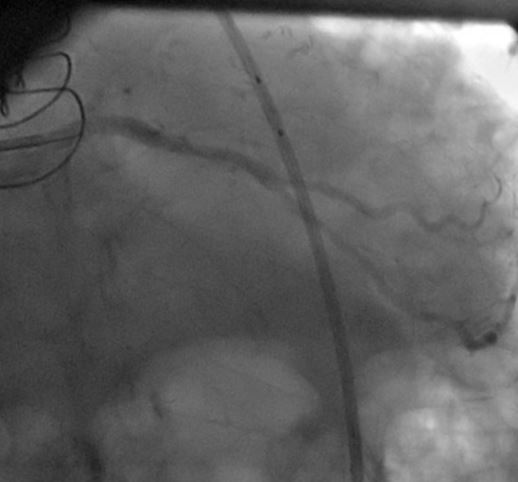

1) LM: subtotal ISR lesion (figure 2, figure 3)